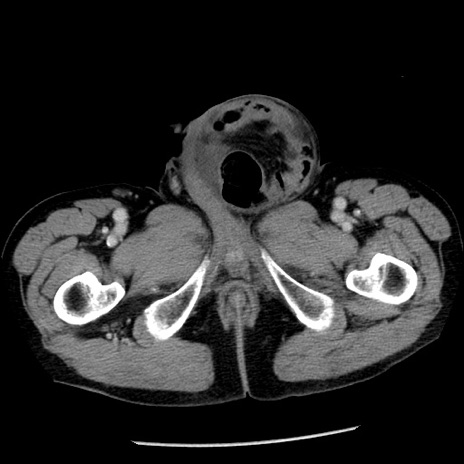

症例26(横断像)

【症例】80歳代男性

【主訴】嘔吐

【現病歴】昨晩2回嘔吐あり、今朝になっても嘔吐あり。来院。

【既往歴】胃潰瘍

【身体所見】意識清明、BT 37.6℃、BP 166/95mmHg、HR 100bpm、SpO2 97%、腹部:平坦・軟、腸蠕動音聴取良好、圧痛なし。

【データ】WBC 21900、CRP 1.46